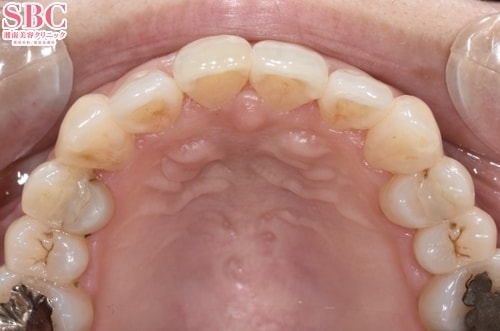

No.318761【美容歯科】の症例写真

施術前

施術後24ヶ月後